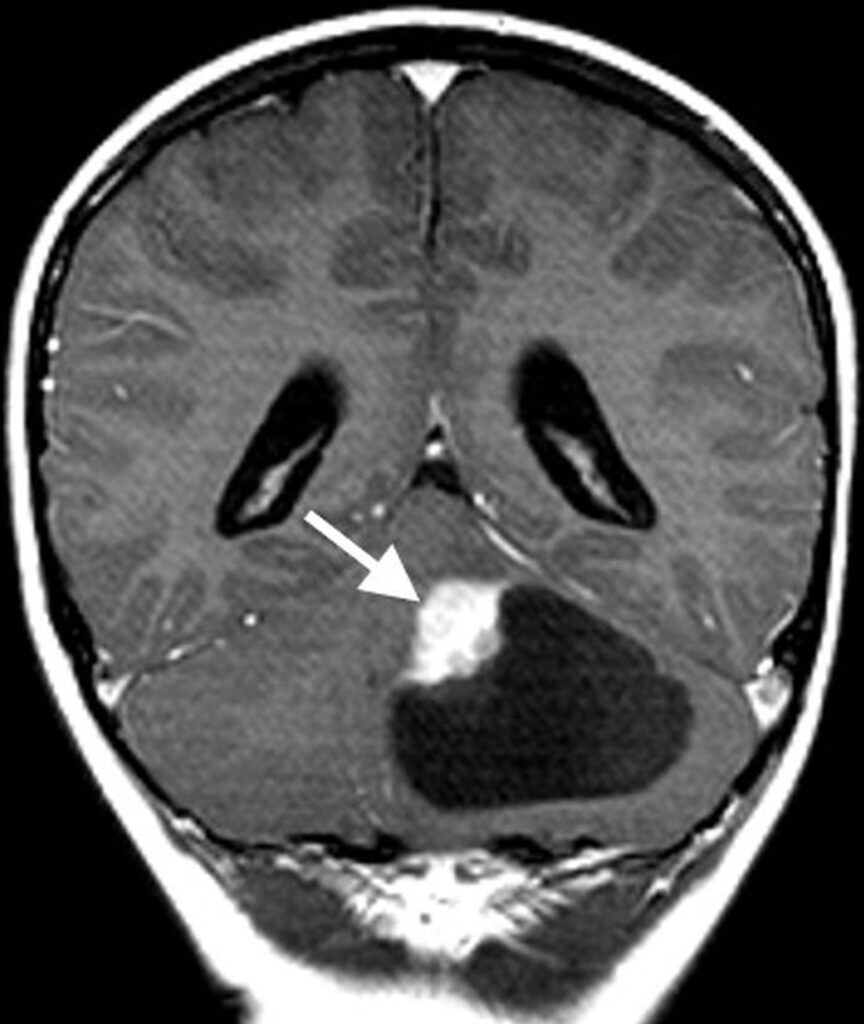

Imaging characteristics for the various subtypes of medulloblastoma are overall similar, reflecting that of densely packed, highly cellular tumors. Masses tend to be spherical in shape and displace adjacent structures, as opposed to the more pliable appearance of ependymomas. Increased density on CT and diffusion restriction on MRI are characteristic of medulloblastomas, reflective of their high cellularity. T2 signal intensity is variable, typically having areas of both increased and decreased T2 signal compared to cerebellar parenchyma. Small intralesional cysts are common, while intralesional hemorrhage and calcification are uncommon, though may occasionally be seen. Enhancement ranges from patchy to more robust solid enhancement [7, 8] (Fig. 1).

On MR spectroscopy, a high-grade tumoral spectrum is evident with increased choline and decreased N-acetyl aspartate peaks. A taurine peak just to the left of the choline peak may be a specific marker for medulloblastoma in the posterior fossa [9].

The frequency of metastatic disease varies depending upon the molecular subtype, ranging from approximately 10% to up to 45% at the time of initial presentation [5]. It is therefore important to image the spine prior to surgical resection and with subsequent surveillance imaging to evaluate for disseminated disease.